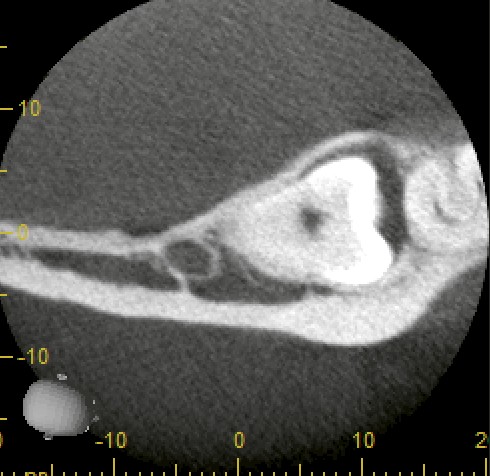

当院にてCT撮影を行ったところ、確かに下歯槽神経に近接していましたが、直接の接触は認められませんでした。

このように、パノラマX線だけでは判断が難しいケースでも、CTによって三次元的に確認することでリスクを正確に分析できます。